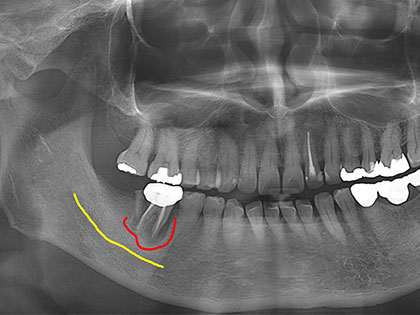

右下6番目が腫れるため、インプラント治療を希望された患者様の症例になります

右下6番目が腫れるためインプラントを希望との事で来院

症例

70代男性

主訴

右下6番目が腫れる

治療経緯

他院で右下6の歯根が破折していると言われたが、そこまで痛くないことと、破折して悪い状態だと認識はあっても抜歯したくないとの事でした。

ただ、そのままにしていますと、破折した周囲には大きな膿が溜まっており(赤い波線)、下歯槽神経(黄色い線)にまで距離が近くなっており、そのままにしておく方が麻痺するリスクを伝え、納得して頂いた上で右下6を抜歯して骨を造成、6、7にインプラントを埋入しました。